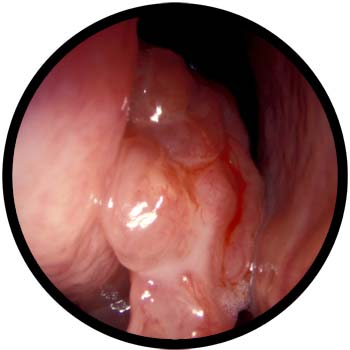

Inverted Papilloma

- Papillomas are wart-like growth arising out of the outer layer of the nasal passage. They tend to grow inwardly and hence the name.

- They occur as a result of an infection caused by Human Papilloma Virus.

- The symptoms are one-sided nasal mass, commonly fleshy in nature. Sometimes it may occur behind a nasal polyp.